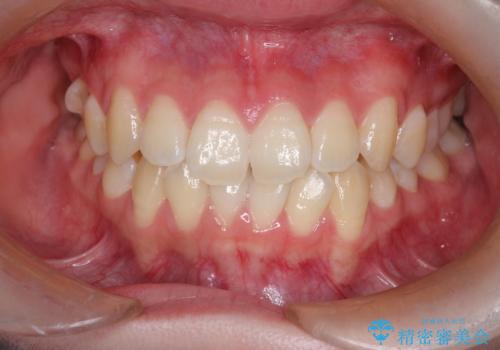

- 右上の小臼歯が大きくねじれており、噛み合わせや見た目に影響を与えている状態でした。診察の結果、インビザライン単独では十分な回転が得られにくいと判断。そのため、基本的な歯列の移動はインビザラインで行いながら、部分的にワイヤー矯正を併用するコンビネーション治療を計画しました。

まず、インビザラインで歯列全体を整えながら、スペースを確保しました。その後、部分ワイヤーを装着し、右上小臼歯の捻転を効率よく改善。ワイヤーの力を活用することで、より確実に歯の向きを整えることができました。治療後は、「しっかり噛めるようになり、見た目も自然になった」と患者様にもご満足いただきました。